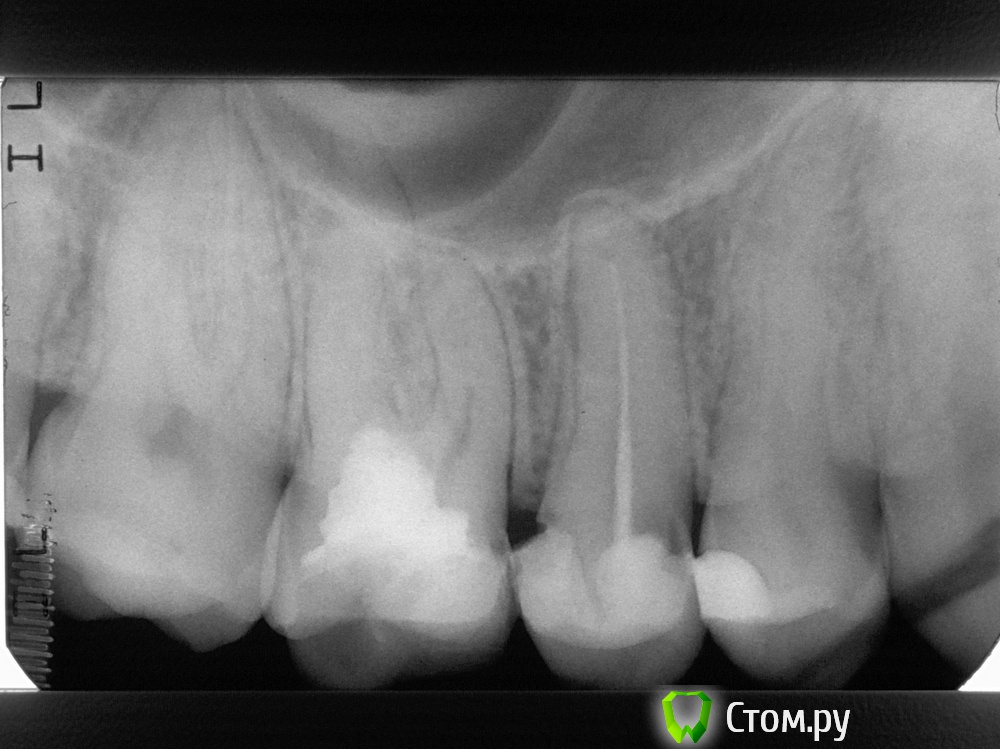

Miriel Опубликовано 13 мая, 2014 Поделиться Опубликовано 13 мая, 2014 Здравствуйте, проконсультируйте, пожалуйста. Полгода назад удалили нерв, запломбировали канал у верхней пятерки. При этом осталась часть старой пломбы. Недели через две начал зуб болеть - реагировать на холодное и просто на прикосновение. Иногда пульсирующая (но не сильная) боль возникала при физических нагрузках (не в смысле орехи зубами колоть, а если пробежаться по лестнице или на лыжах прокатиться). Месяца через три на десне обнаружилась припухлость примерно 4-5 мм, которая медленно, но верно увеличивается. Теперь сам зуб не болит, только десна при прикосновении к ней или к щеке. Лечащий врач (и другие, с которыми консультировались) рекомендуют еще подождать. Типа рассосется само, но у меня что-то сомнения на этот счет имеются. Наверное, надо перепломбировать каналы, но не знаю к кому бы обратиться (в Москве). Снимок прилагается. Ссылка на комментарий

Гарриевич Опубликовано 13 мая, 2014 Поделиться Опубликовано 13 мая, 2014 Добрый день. Лечение проведено неадекватное, ждать смысла нет. Зуб нужно передечивать. Убирать старую пломбу и скорее всего покрывать вкладкой и коронкой. 2 Ссылка на комментарий